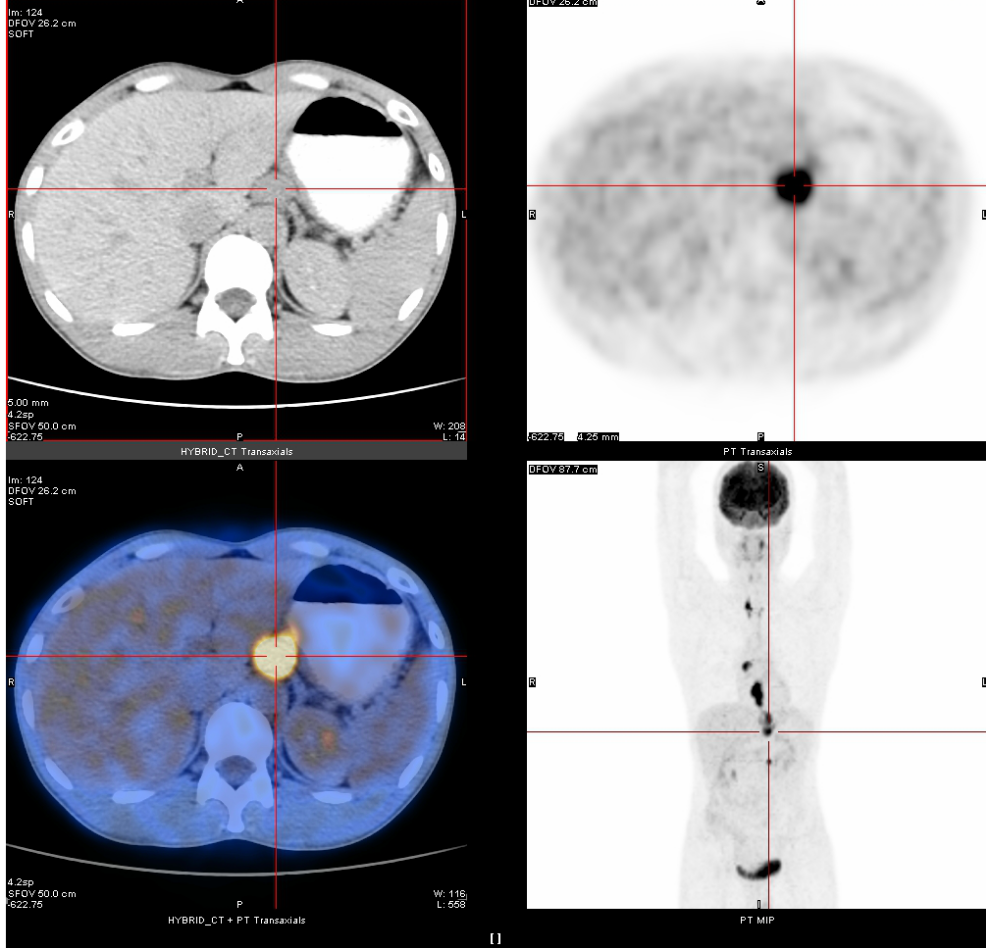

2020年3月13日

全身PET-CT示:1、食管胸中下段管壁不规则增厚,代谢增高,考虑食管癌。2、上纵隔胸廓入口区气管两旁、右下肺静脉后方、贲门区、肝胃间隙、降主动脉后方、膈肌脚后方、腹膜后腹主动脉左旁(左肾门下方平面)见多发高代谢肿大淋巴结,考虑淋巴结转移,建议随访复查。3、右肺上叶前段胸膜下小结节影,代谢未见增高,建议随访复查。4、右肺下叶外基底段条索影,考虑慢性炎性改变。5、双侧上颌窦轻度慢性炎症。6、双侧颈部多发小结节影,代谢未见增高,考虑淋巴结慢性炎性增生。7、肝左叶内侧段小钙化灶。